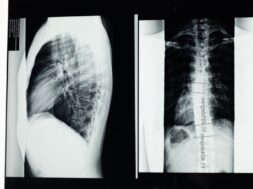

Η σκολίωση είναι μια κοινή πάθηση της σπονδυλικής στήλης που απαντάται συχνά στους εφήβους. Eκατομμύρια νέες περιπτώσεις της πάθησης διαγιγνώσκονται κάθε χρόνο, με την πλειοψηφία τους να αναγνωρίζεται ως ιδιοπαθής σκολίωση – ένας τύπος σκολίωσης που εμφανίζεται σε παιδιά μεταξύ 10 και 12 ετών.

Τα κοινά σημάδια της σκολίωσης περιλαμβάνουν ανομοιόμορφους ώμους ή γοφούς, αλλά γενικά είναι μια ανώδυνη κατάσταση που μπορεί να περάσει απαρατήρητη μέχρι να γίνει κάποια εξέταση ρουτίνας.